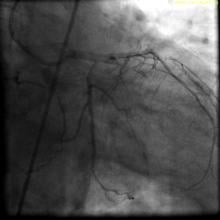

Chandan Devireddy, M.D., offers insights about what he saw as the top take aways from the 2019 Transcatheter Cardiovascular Therapeutics (TCT) annual meeting. He is cath lab director at Emory University Hospital Midtown, associate professor of medicine of interventional cardiology at Emory University, and chairperson for the Society of Cardiovascular Angiography and Interventions (SCAI) Communications Committee.

Devireddy said his key take aways from TCT 2019 were:

• The poor results of the Boston Scientific Acurate Neo self-explaining TAVR system compared to the current devices on the U.S. market;

• Results of the Abbott Portico TAVR system;

• Levant Trial shows no increased mortality due to use of a paclitaxel-coated balloon; and

• CT study of TAVR valve leaflet thrombosis.